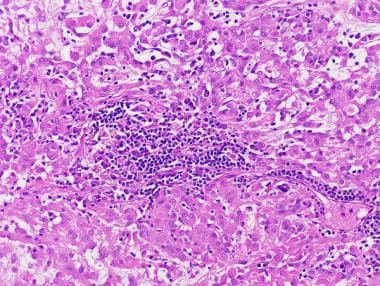

脊索样胶质瘤在粘液性、常空泡化的高碘酸希夫[PAS]阳性背景下显示出索状和簇状上皮样肿瘤细胞。在弦突排列不太突出的区域,肿瘤细胞可以形成固体片,细胞外粘蛋白减少。细胞本身一般呈椭圆形,有大量嗜酸性胞浆,大小适中,外观相对均匀。该肿瘤具有低度的组织学外观,没有核多形性或有丝分裂活性。间质淋巴浆细胞浸润和罗素小体通常与这些肿瘤有关,这为脊索样胶质瘤的分类以及将它们与下丘脑中出现的其他胶质瘤区分开来提供了有用的线索。见下图。

带有大量炎症细胞的脊索样胶质瘤。

脊索瘤胶质瘤的特征是嵌入粘液背景的上皮样细胞索,让人想起脊索瘤。其脑内位置排除了后一种可能性。